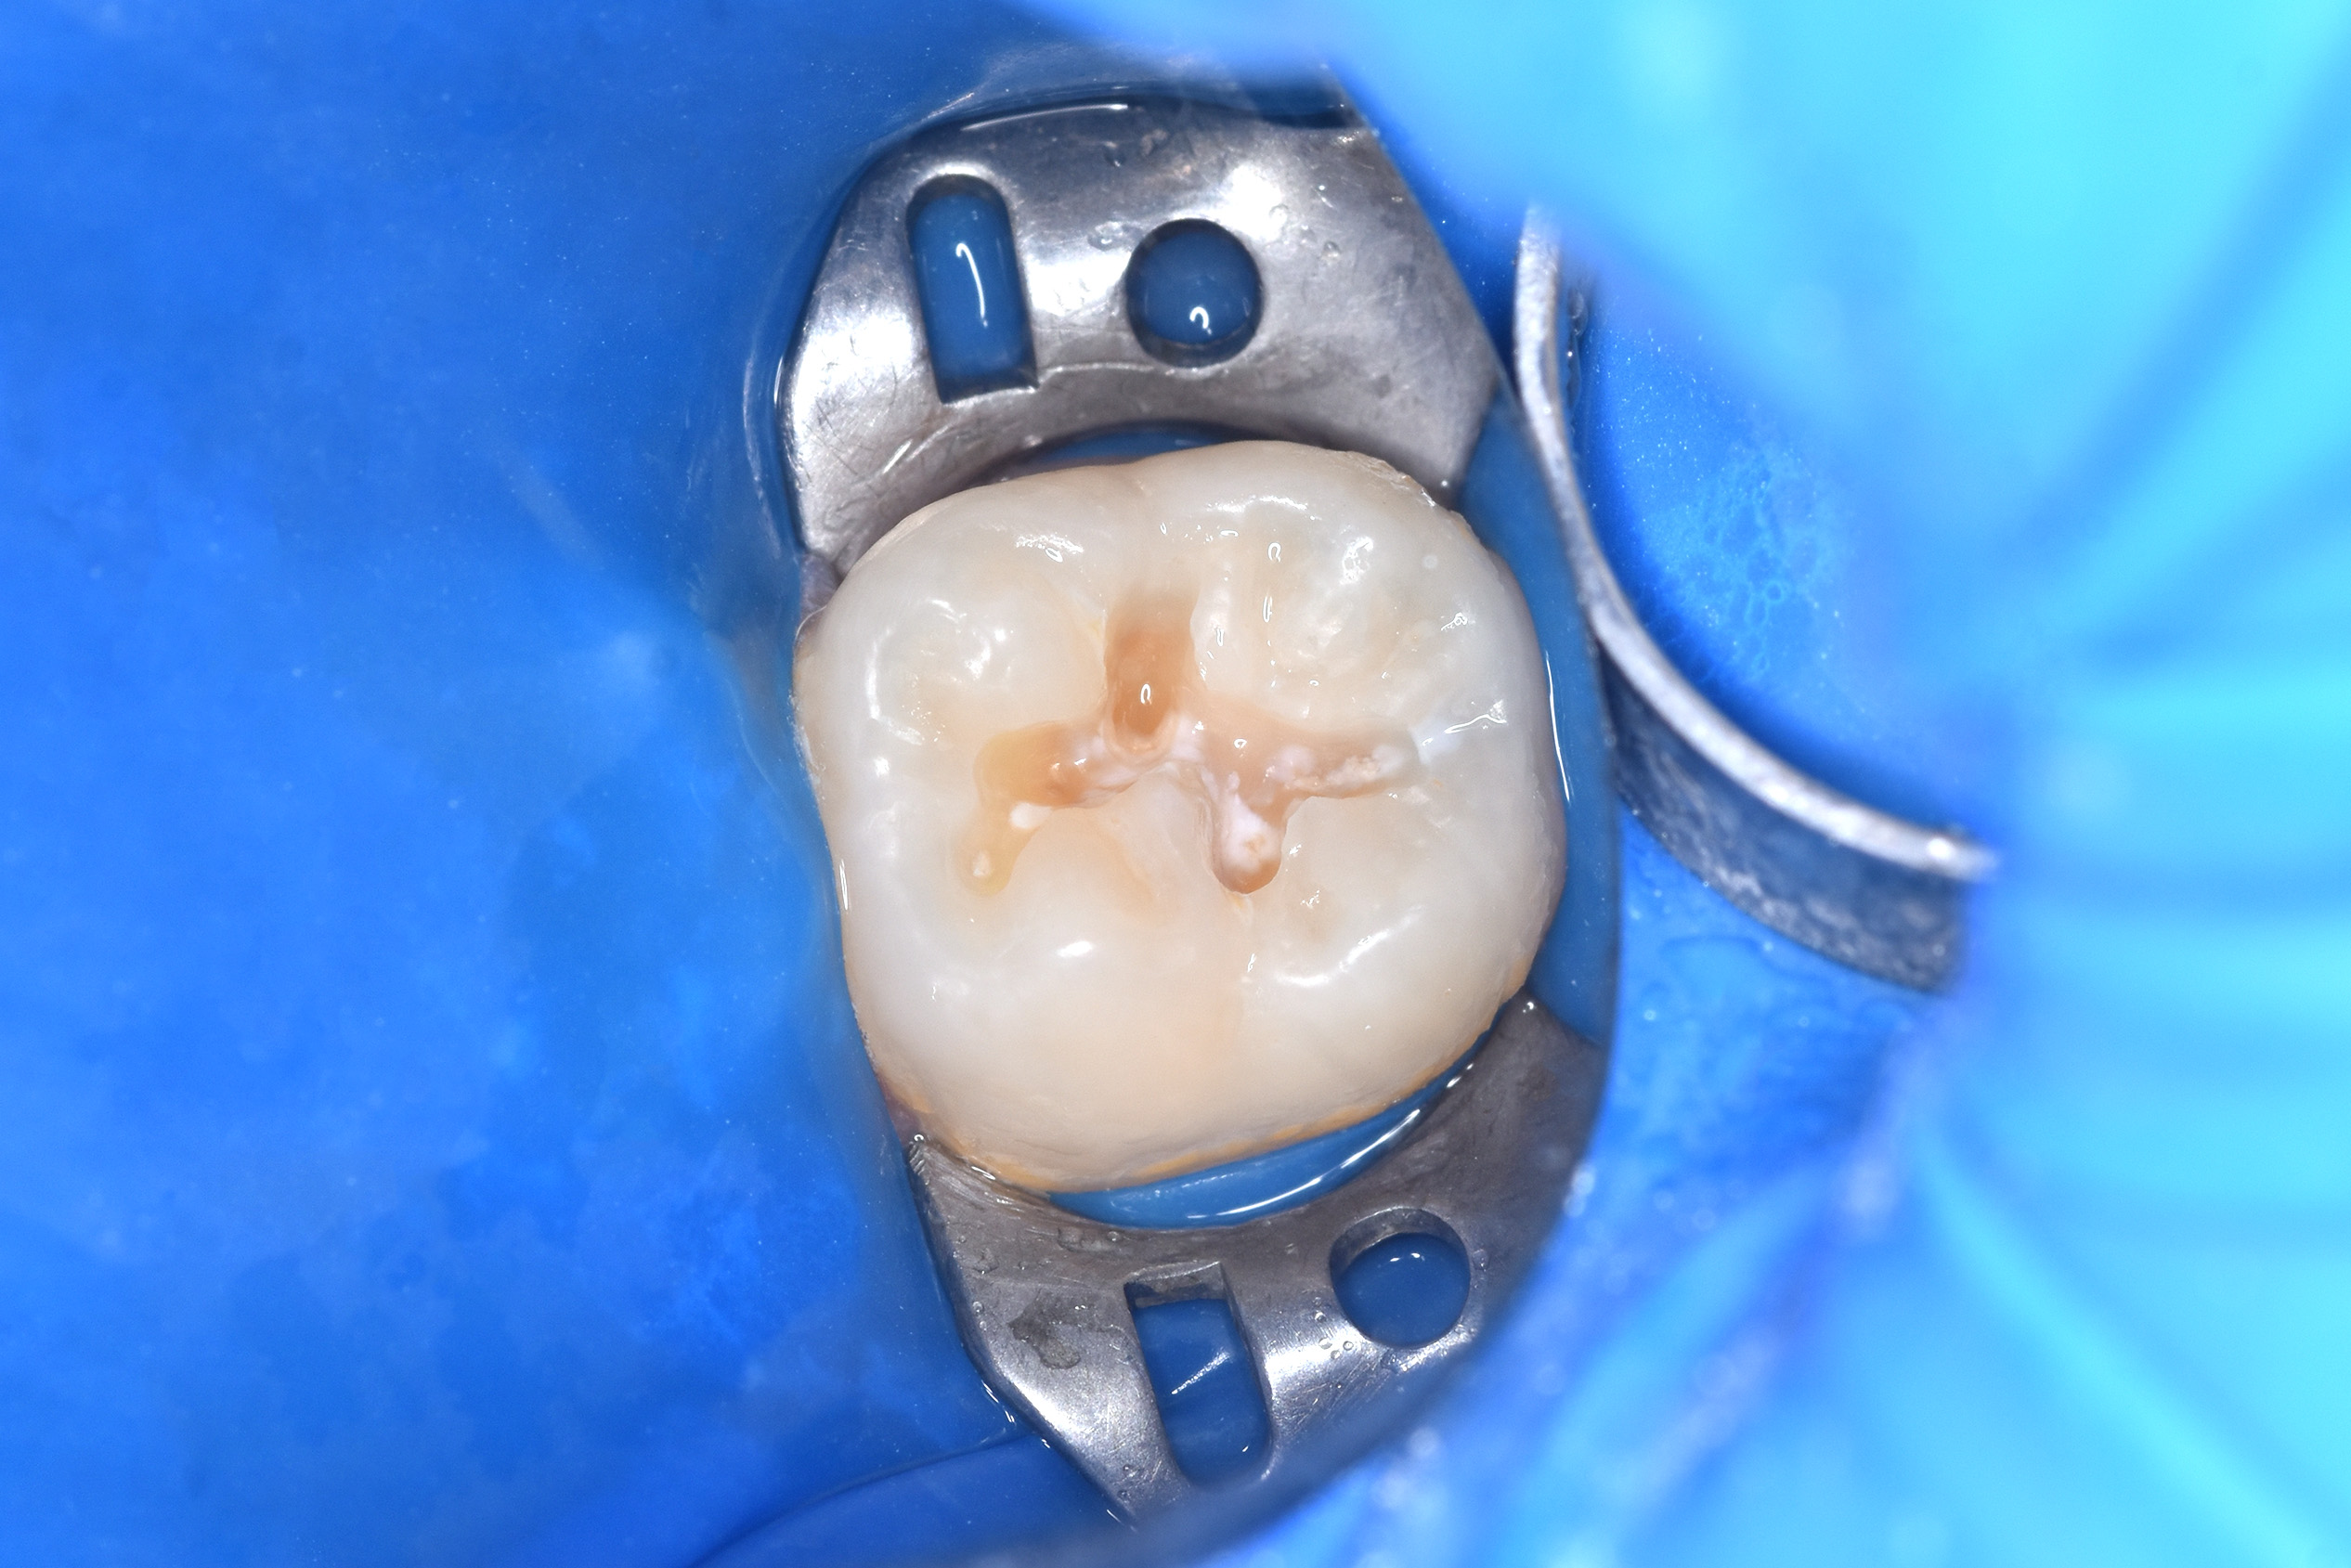

13 лет. Кариес постоянного зуба. Жалобы на сладкое.

Лечение кариеса

Зуб восстановлен пломбировочным материалом.